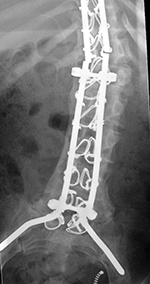

| Extensive lumbar spine fusion with pedicle screws and rods |

| A laminectomy has been performed from T12-L5. Pedicle screws and rods are at L3-S1 from the initial lower lumbar spine fusion. Later surgery added pedicle screws and rods at T12-L3, and L3-L5 with a crosslink at L2. |